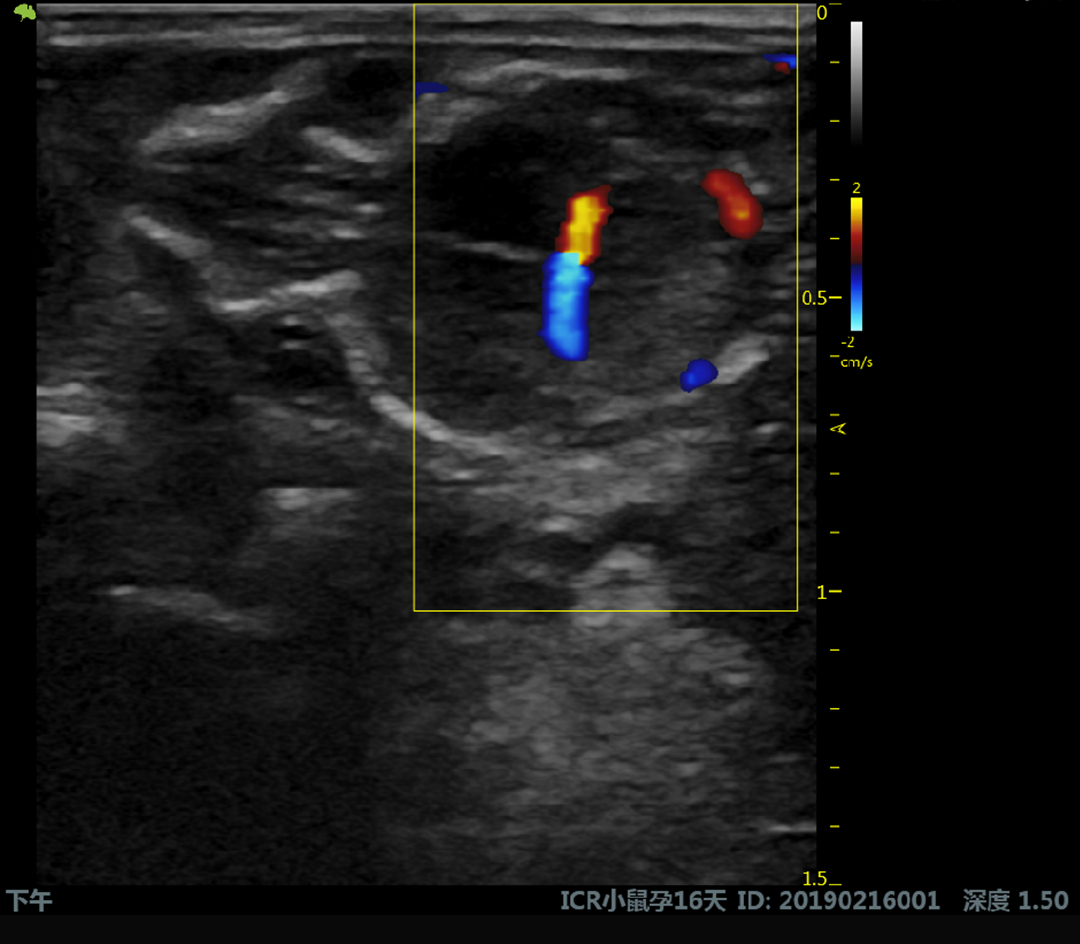

Le V6 LAB est un système d’échographie préclinique ultra-haute fréquence dédié à l’imagerie fonctionnelle et structurelle du petit animal.

Il combine traitement RF avancé, algorithmes d’imagerie Ultra HD et sondes haute fréquence pour fournir

des données fiables, reproductibles et exploitables en recherche.

Reproduction & développement

Doppler couleur, pulsé et puissance

Doppler couleur, Doppler pulsé et Doppler puissance